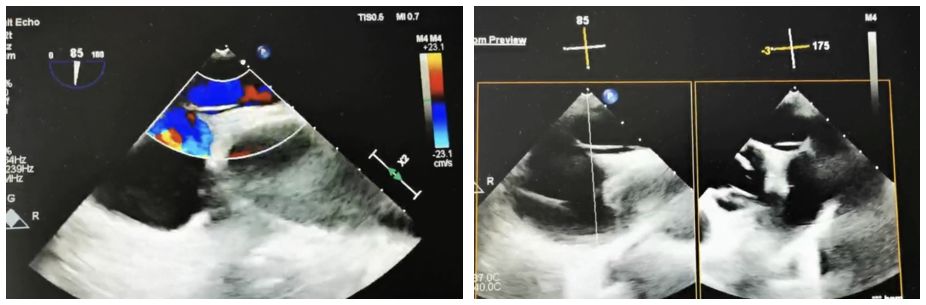

Case Information: A 60-year-old male patient was admitted to the neurology department after experiencing "left-sided limb weakness". The patient underwent a routine transesophageal echocardiogram (TEE), which revealed a patent foramen ovale (PFO) (congenital type, 2.4mm in width, 33mm in length, with moderate shunting). Right heart echocardiography and bubble tests confirmed a grade II shunt.

Clinical Strategy: We chose the BDPFO-I 2828 symmetrical occluder to ensure optimal closure. During the release phase, DSA imaging was used for positioning, while ultrasound guidance was primarily employed to ensure accurate deployment.

Case Summary: Due to the length of the tunnel, conventional catheter guidewires and septal puncture sheath support were not effective. Specifically, a coronary guidewire combined with a septal puncture sheath was used in this case and successfully crossed the septum. When using traditional metallic occluders for long tunnel PFO closures, the rigid material and fixed waist position often prevent the left disc from fully expanding. This can cause the disc to be pulled into the tunnel, leading to residual shunting. In contrast, the biodegradable occluder, with its strong compliance, allowed the waist to fully fill the tunnel and achieve an effective closure.